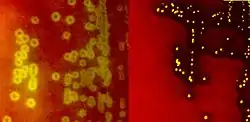

Species of Streptococcus are classified based on their hemolytic properties.[10] Alpha-hemolytic species cause oxidization of iron in hemoglobin molecules within red blood cells, giving it a greenish color on blood agar. Beta-hemolytic species cause complete rupture of red blood cells. On blood agar, this appears as wide areas clear of blood cells surrounding bacterial colonies. Gamma-hemolytic species cause no hemolysis.[11]

When alpha-hemolysis (α-hemolysis) is present, the agar under the colony will appear dark and greenish due to the conversion of hemoglobin to green biliverdin. Streptococcus pneumoniae and a group of oral streptococci (Streptococcus viridans or viridans streptococci) display alpha-hemolysis. Alpha-hemolysis is also termed incomplete hemolysis or partial hemolysis because the cell membranes of the red blood cells are left intact. This is also sometimes called green hemolysis because of the color change in the agar.

Beta-hemolysis (β-hemolysis), sometimes called complete hemolysis, is a complete lysis of red cells in the media around and under the colonies: the area appears lightened (yellow) and transparent. Streptolysin, an exotoxin, is the enzyme produced by the bacteria which causes the complete lysis of red blood cells. There are two types of streptolysin: Streptolysin O (SLO) and streptolysin S (SLS). Streptolysin O is an oxygen-sensitive cytotoxin, secreted by most group A Streptococcus (GAS), and interacts with cholesterol in the membrane of eukaryotic cells (mainly red and white blood cells, macrophages, and platelets), and usually results in beta-hemolysis under the surface of blood agar. Streptolysin S is an oxygen-stable cytotoxin also produced by most GAS strains which results in clearing on the surface of blood agar. SLS affects immune cells, including polymorphonuclear leukocytes and lymphocytes, and is thought to prevent the host immune system from clearing infection. Streptococcus pyogenes, or GAS, displays beta hemolysis.